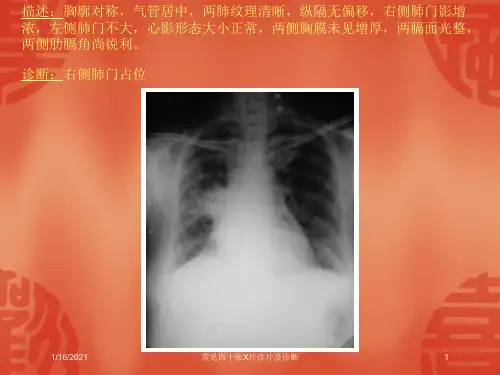

胸部X片主要用于观察肺部、胸膜、纵隔等 结构,是诊断肺部和胸膜疾病的重要手段 。